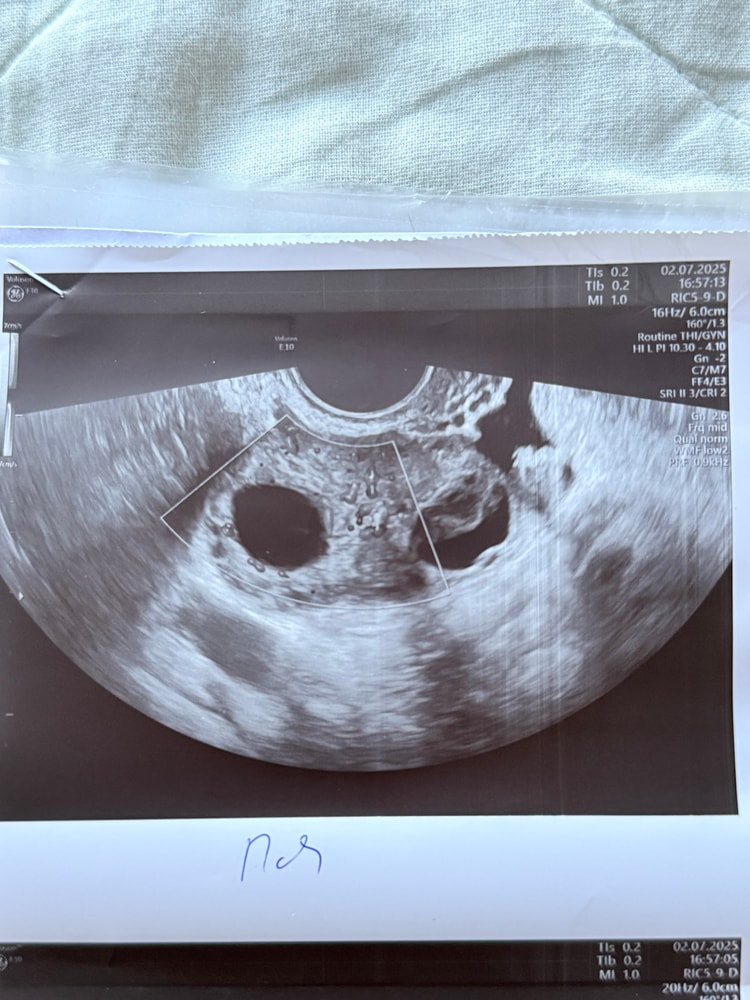

Сегодня 25 ДЦ, картина такая

Лерка, как узист объяснила, есть кровоток на большом фолликуле, но, она тоже сомневается, но на 18 ДЦ, было ощущение, что О была